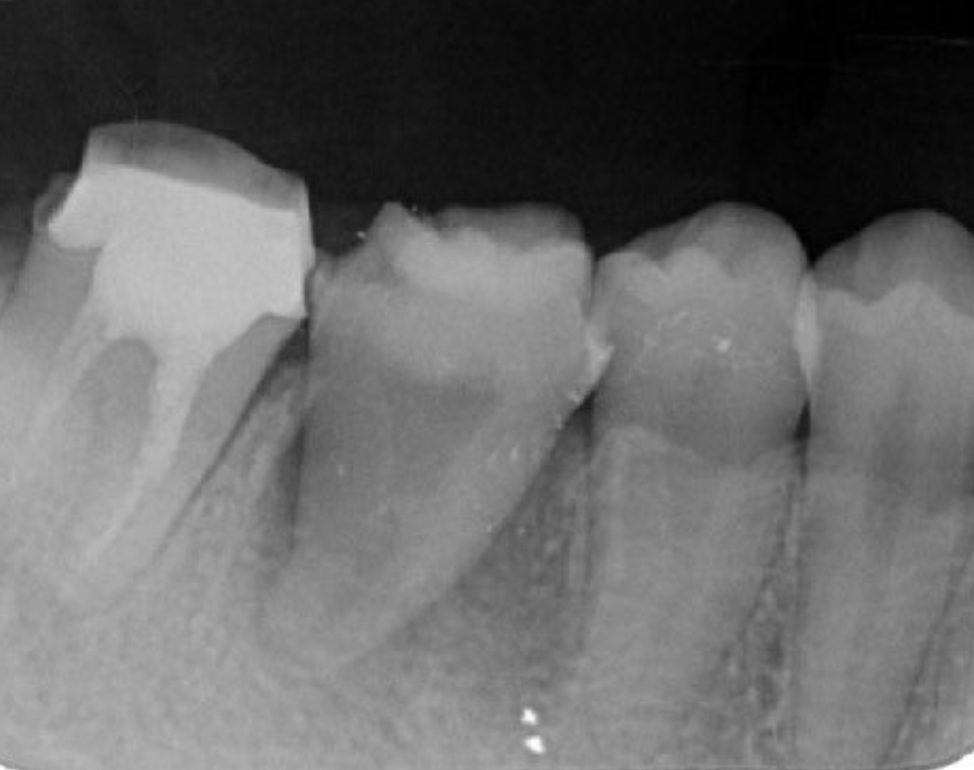

Figure 2.Pre-treatment X-ray findings. A cystic lesion was found in the mesial and distal roots apex, and root nodule of #46.

Figure 3.Preoperative intraoral findings. A metal crown was inserted at #46 and bleeding on probing during the periodontal pocket examination was noted.